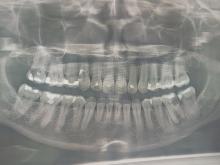

There are several possible causes of bleeding gums. Some of the most common include:

1.)Poor dental hygiene: If you do not brush and floss regularly, plaque can build up on your teeth and cause your gums to become inflamed and bleed.

2.)Gum disease: Gum disease, also known as periodontal disease, is an infection of the gums that can cause them to become swollen, red, and prone to bleeding.